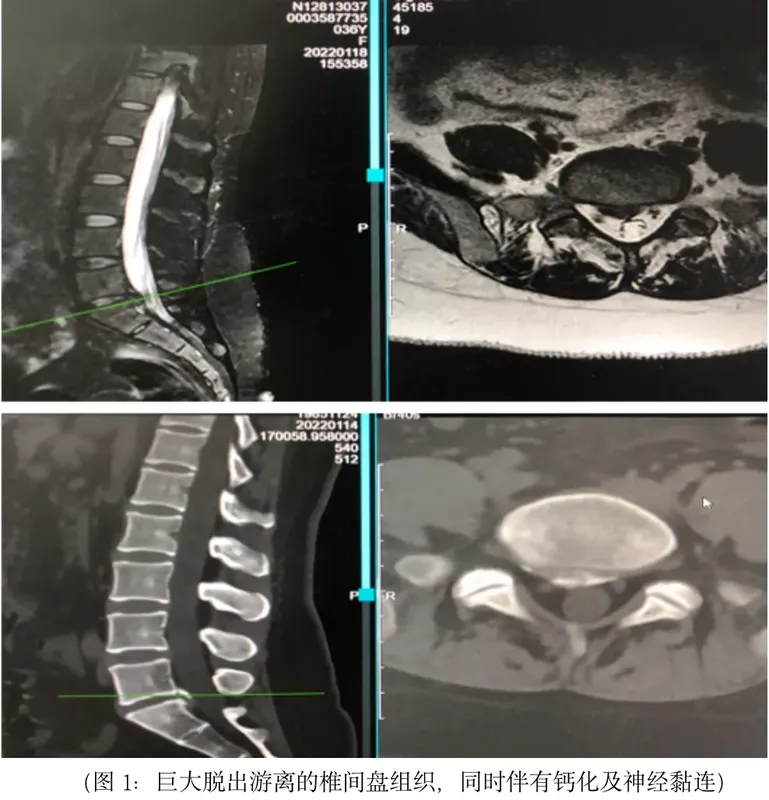

近日,上海市第一人民醫(yī)院骨科臨床醫(yī)學(xué)中心脊柱二科(北)主任付強(qiáng)團(tuán)隊(duì)運(yùn)用全脊柱內(nèi)鏡聯(lián)合脊柱專用激光,為一位因惡性骨腫瘤接受過5次手術(shù)、導(dǎo)致腰椎管內(nèi)神經(jīng)嚴(yán)重粘連的巨大腰椎間盤突出患者實(shí)施了手術(shù)治療。手術(shù)通過一個僅5毫米的切口入路,以激光光纖激發(fā)脊柱專用激光,分離、消融、氣化突出椎間盤神經(jīng)周圍的黏連組織,隨即順利摘除脫出的椎間盤。手術(shù)出血僅5毫升,用時23分鐘即告完成。這也是上海市第一人民醫(yī)院脊柱外科完成的首例脊柱內(nèi)鏡聯(lián)合脊柱專用激光手術(shù)。此次接受手術(shù)的患者今年36歲,之前因雙下肢患惡性骨腫瘤,曾在外院反復(fù)行5次手術(shù),在長期的術(shù)后化療與激素治療副作用影響下,體重達(dá)200余斤。兩周前,這位患者突然出現(xiàn)右下肢放射性疼痛與麻木,并放射至右側(cè)足底,以至于無法下地行走。上海市第一人民醫(yī)院骨科臨床醫(yī)學(xué)中心脊柱二科(北)主任付強(qiáng)團(tuán)隊(duì)接診了這位患者。入院檢查發(fā)現(xiàn),患者所患纖維肉瘤存在全身轉(zhuǎn)移可能,一般情況差,其腰椎L5-S1間存在巨大椎間盤脫出,合并明顯鈣化,且腰椎管內(nèi)存在嚴(yán)重的神經(jīng)黏連。手術(shù)團(tuán)隊(duì)討論認(rèn)為,常規(guī)開放腰椎融合手術(shù)屬于大手術(shù),若實(shí)施開放腰椎融合手術(shù)入路,強(qiáng)行摘除椎間盤,分離黏連組織的過程會讓患者術(shù)中發(fā)生神經(jīng)損傷的風(fēng)險大大增加,且容易發(fā)生術(shù)后感染。在仔細(xì)評估并與患者及家屬溝通后,專家團(tuán)隊(duì)決定采用經(jīng)椎板間全脊柱內(nèi)鏡聯(lián)合專用激光手術(shù)為其實(shí)施治療。手術(shù)當(dāng)日,在手術(shù)室護(hù)理團(tuán)隊(duì)和麻醉科的大力配合下,患者很快完成術(shù)前準(zhǔn)備。手術(shù)團(tuán)隊(duì)通過一個僅有5毫米的切口,精準(zhǔn)穿刺至突出椎間盤,建立工作通道并置入脊柱內(nèi)鏡。在50倍的放大視野下,可以看到患者腰椎管神經(jīng)組織周圍黏連十分嚴(yán)重,神經(jīng)根腹側(cè)有巨大脫出的椎間盤組織,同時伴有鈣化。手術(shù)團(tuán)隊(duì)通過工作通道,置入預(yù)先連接好的激光光纖,激發(fā)脊柱專用激光,利用激光分離、消融及氣化功能,切除了突出椎間盤神經(jīng)周圍的黏連組織。手術(shù)用時僅23分鐘,術(shù)中出血僅5毫升。據(jù)專家介紹,脊柱內(nèi)鏡手術(shù)的難點(diǎn)之一就是術(shù)中止血,手術(shù)出血會造成視野障礙,增加手術(shù)時間及手術(shù)風(fēng)險。傳統(tǒng)射頻方式在術(shù)中需要緊貼組織,使得局部組織溫度升高至60℃引起蛋白變性,達(dá)到止血目的。但由于電能轉(zhuǎn)化為熱能速度較慢,組織局部溫度升高慢,止血效率較低。脊柱專用激光能量高,光能轉(zhuǎn)換為熱能速度更快,能量可被組織快速吸收并達(dá)到止血溫度,輔以內(nèi)鏡技術(shù),有著傷口較小、出血較少、術(shù)后恢復(fù)快等優(yōu)勢。前期實(shí)驗(yàn)研究及臨床經(jīng)驗(yàn)發(fā)現(xiàn),激光手術(shù)患者術(shù)后腰痛癥狀更輕,椎間盤的術(shù)后炎性反應(yīng)也更低。此次手術(shù)不僅展現(xiàn)了脊柱二科團(tuán)隊(duì)精湛的診治水平,同時也體現(xiàn)了以患者為中心、為患者提供個性化、精準(zhǔn)化醫(yī)療服務(wù)的理念。